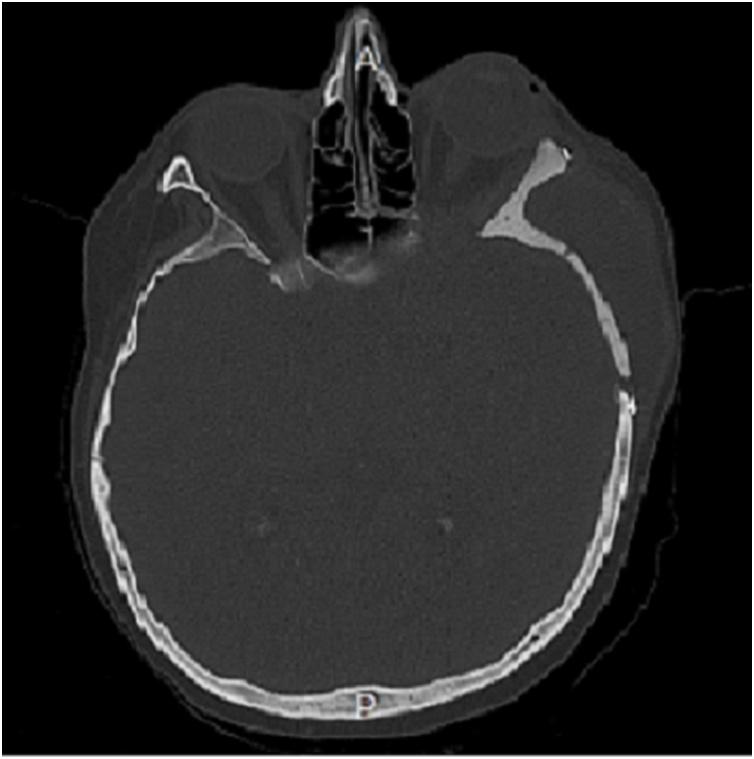

我们描述了一例复杂的额眶颅底转移瘤病例,该病例需要进行颅骨重建,我们采用单步手术和定制植入物进行治疗。我们的手术包括两个步骤:第一步,我们在先前基于高分辨率骨CT扫描构建的3D虚拟模型上进行“虚拟”开颅手术。第二步,即实际手术过程,患者接受使用定制聚甲基丙烯酸甲酯颅骨成形术植入物进行颅骨缺损的切除和重建。报告了为期三个月的临床和影像学随访情况,记录了切除范围和良好的美学效果。

We describe a single case of a complex fronto-orbital skull base metastasis requiring skull bone reconstruction that we treated with a single-step surgery and custom-made implant. Our procedure consists of two steps: in the first one, we perform a "virtual" craniotomy on a 3D phantom model previously built on a high-resolution bone CT scan. In the second step, the actual surgical procedure, the patient undergoes the resection and reconstruction of the cranial defect with an implant of PMMA custom-made cranioplasty. A three-month clinical and radiological follow-up is reported, which documented the extent of resection and good aesthetic results.